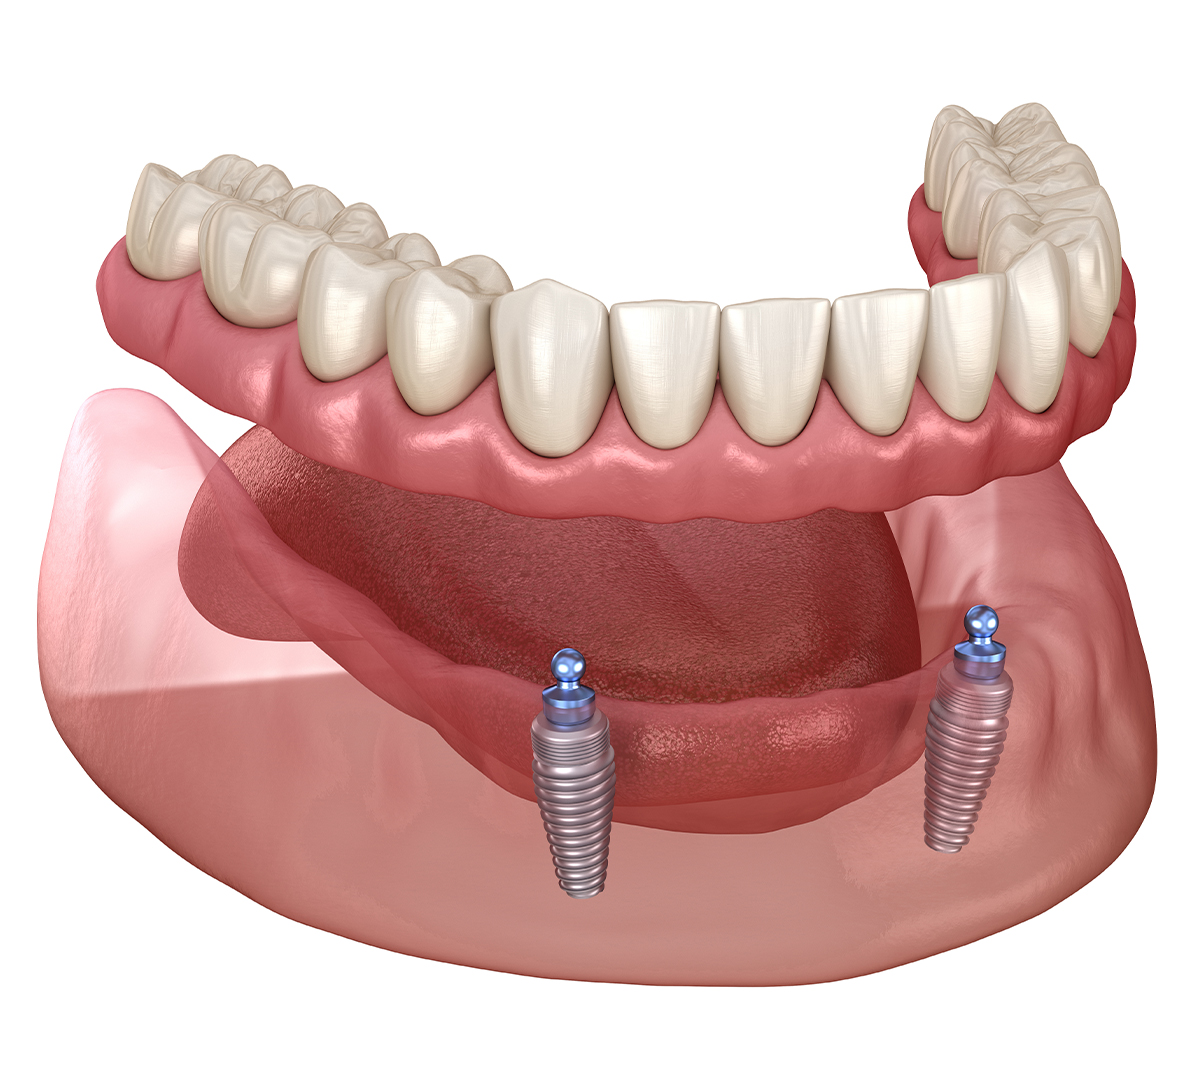

Le principe des implants supports de prothèses

L’implantologie permet de stabiliser une prothèse amovible en insérant stratégiquement des implants dentaires dans la mâchoire. En général, deux implants sont placés parallèlement dans la symphyse mentonnière (zone antérieure de la mandibule). Ces implants sont ensuite dotés d’un système de fixation à boutons-pression, permettant de maintenir solidement la prothèse tout en la rendant amovible pour un entretien facile.

Une fois l’ostéointégration complète, la prothèse amovible est fixée aux implants via des boutons-pression, garantissant un maintien optimal.